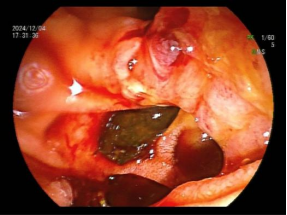

十二指肠乳头藏匿“隐秘角落” ,多发憩室让取石之路“荆棘丛生”,意味着这是一台高难度ERCP,面对这一复杂情况,黄华丽主任凭借其10余年丰富的ERCP实战经验,决定迎难而上,为患者实施ERCP取石术。术前黄华丽主任带领团队对患者的病情进行了复盘分析,鉴于传统手术取石风险较高,内镜微创手术伤害小,因此决定冒险采用ERCP取石术。充分沟通手术的必要性及十二指肠降部解剖结构异常导致手术难度,制定了详细的手术方案,并对手术过程中可能出现的各种情况进行了充分的预判和应对准备。患者及家属果断同意行ERCP术。术中,黄华丽主任通过巧妙调整内镜角度、最终找到藏匿在憩室旁边被挤压的十二指肠乳头,因结构异常只能长镜身插管,成功插管进行造影以明确结石的位置、大小和数量,取石球囊反复取石,成功将患者胆总管内的结石一一取出(见图2、3、4、5)。整个取石过程顺利,未出现明显并发症。患者术后恢复情况良好,未出现明显的疼痛和不适。患者术后腹痛、发热症状完全消失,黄疸逐渐消退。

图5 取出的结石